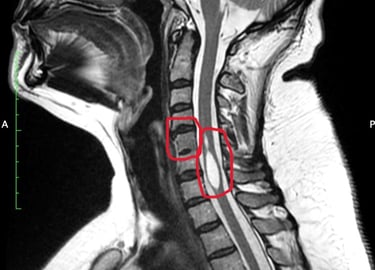

La fundación nació después de que Audry, nuestra CEO, pasara tres largos años de negación por parte de los médicos que no reconocían sus síntomas ni enfermedades. Después de ver alrededor de 20 doctores en Canadá, fue en el mes de marzo del año 2023 cuando conoció un médico Genetista, que logró tener un diagnóstico confirmado de las enfermedades que padece: Siringomielia, Síndrome de Klippel-Feil y Síndrome de Médula Anclada.